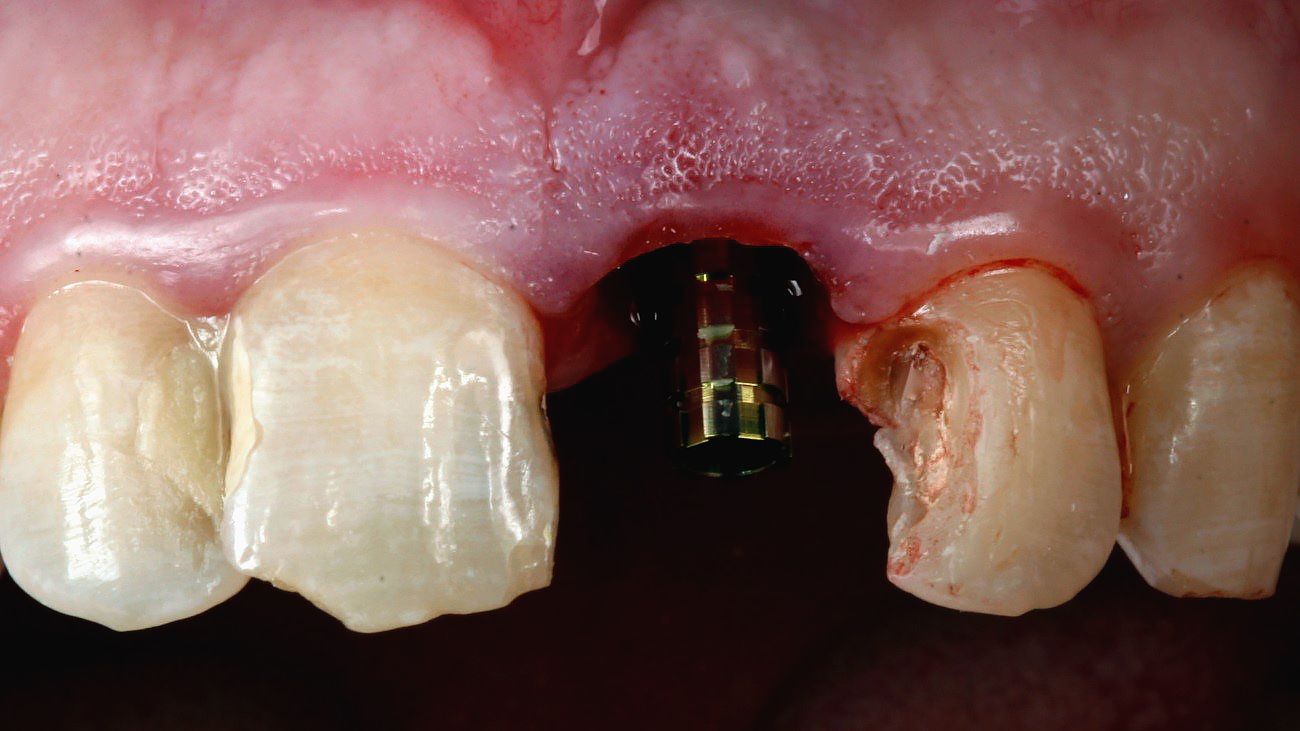

Unexpectedly, 18 days after the implant placement, the patient had a cut-contusion lesion with loss of substance of the lower lip. He reported having undergone direct physical assault with a blunt object. The examination showed considerable mobility of the provisional implant prosthesis, albeit without signs of inflammation in the region. The provisional prosthesis was removed and, to our pleasant surprise, it was found that implant stability had been maintained and only the prosthesis screw had loosened due to the trauma suffered. Immediately, in a single step, we proceeded with the preparation of the ceramic prosthetic parts and the impression of the whole region, including the implant, as described below (Figs. 10,11).

Prosthetic procedure

The excellent treatment surface of the Roxolid® SLActive® implant allows definitive implant activation to be initiated within 21 days. In this case, however, due to the circumstances, the rehabilitation procedures began at 18 days. Ceramic fragments were prepared for teeth 12, 11 and 21 with diamond drills and ultrasonic tips; tissue control was carried out in the region and the impression post was installed on the implant and customized, so that the surrounding soft tissue could be accurately reproduced (Figs. 12,13). The CADCAM system technology allows amazing accuracy, providing better functional and economic benefits to patients. The implant prosthesis was made following the CARES® approach on the Straumann® Variobase® abutment, which allows exact engagement of the coping to the Straumann® Variobase® abutment with its four engaging grooves. For scanning and modelling of the case, the Dental Wings platform was used to design the implant prosthesis and the ceramic for the adjacent teeth (Figs. 14,15). The milling was done in zirconia for later application of ceramic coverage, characterization and customization of the elements. The parts were tested in the mouth and, after adjustment, were properly etched and cemented (Figs. 16-21).